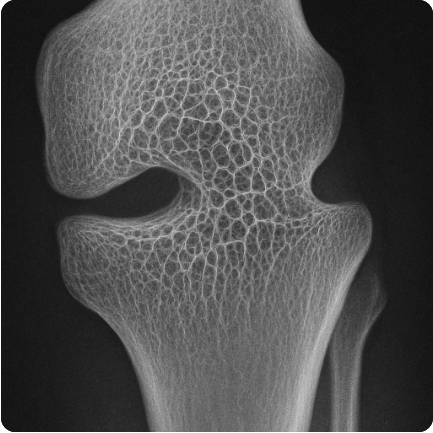

검출기의 해상도 차이는 최종 의료 영상의 품질에 매우 큰 영향을 미치며, 육안으로도 확연한 차이를 보일 수 있습니다. 고해상도 검출기를 사용한 영상은 저해상도 검출기를 사용한 영상에 비해 다음과 같은 특징을 가집니다. 첫째, 향상된 선명도와 디테일입니다. 고해상도 검출기는 작은 구조물들을 더 많은 픽셀로 표현하기 때문에 영상이 전반적으로 더 선명하고 깨끗하게 보입니다. 미세한 혈관 분지, 작은 뼈의 골소주 구조, 장기 표면의 미세한 변화 등 저해상도 영상에서는 흐릿하게 보이거나 아예 구별하기 어려웠던 디테일들이 고해상도 영상에서는 또렷하게 나타납니다. 둘째, 작은 구조물 식별 능력 향상입니다. 해상도가 높을수록 영상에서 표현할 수 있는 가장 작은 크기의 구조물이 작아집니다. 이는 임상적으로 매우 중요한데, 예를 들어 초기 단계의 미세한 병변이나 작은 결절 등을 놓치지 않고 발견하는 데 유리합니다. 저해상도 영상에서는 여러 작은 구조물이 하나의 픽셀로 뭉쳐져 보이거나 아예 감지되지 않을 수 있습니다. 셋째, 명확한 구조 경계 표현입니다. 고해상도 영상은 서로 다른 조직이나 구조물 간의 경계를 더 날카롭고 명확하게 표현합니다. 이는 병변의 정확한 크기, 형태, 주변 조직으로의 침범 여부 등을 평가하는 데 중요한 정보를 제공합니다. 저해상도 영상에서는 경계가 불분명하여 평가에 어려움이 있을 수 있습니다. 하지만 해상도를 높이는 것이 항상 장점만 있는 것은 아닙니다. 검출기 소자 크기가 작아지면 각 소자가 받는 X선 신호량도 줄어들어 노이즈에 더 취약해질 수 있으며, 이는 영상의 입자감을 증가시켜 대비 분해능을 저하시킬 수도 있습니다. 따라서 고해상도 검출기 기술은 노이즈 저감 기술과 함께 발전하여 해상도 향상과 노이즈 최소화의 균형을 이루는 것이 중요합니다. 영상의학 장비 도입 시 검출기의 해상도 사양을 꼼꼼히 확인하는 것은 기대할 수 있는 영상 품질 수준을 가늠하는 중요한 기준이 됩니다.

고해상도 검출기를 통해 얻어진 영상은 영상의학 진단의 정확성을 비약적으로 향상시키는 데 결정적인 역할을 합니다. 영상에 담긴 풍부하고 세밀한 정보는 의료진이 보다 정확하고 자신감 있는 진단을 내릴 수 있도록 지원합니다. 첫째, 미세 병변의 조기 및 정확한 발견입니다. 고해상도 영상은 크기가 매우 작거나 형태가 불규칙한 초기 단계의 병변(예: 폐의 미세 결절, 유방의 미세 석회화, 작은 용종 등)을 더욱 명확하게 시각화합니다. 저해상도 영상에서는 보이지 않거나 의심하기 어려웠던 병변을 조기에 발견함으로써 적절한 치료 시기를 확보하고 환자의 예후를 개선하는 데 크게 기여합니다. 둘째, 병변 특성의 상세 평가입니다. 병변이 발견된 후에도 고해상도 영상은 그 형태, 경계의 날카로움, 내부 구조의 균질성 여부, 주변 조직과의 관계 등을 더 상세하게 보여줍니다. 이러한 상세 정보는 악성 종양과 양성 병변을 감별하거나, 종양의 침윤 정도를 평가하고 병기를 설정하는 데 필수적입니다. 예를 들어, 종양의 미세한 침상 돌기나 불규칙한 경계는 악성을 시사하는 중요한 소견일 수 있으며, 이는 고해상도 영상에서만 명확하게 관찰될 수 있습니다. 셋째, 복잡한 해부학적 구조의 정밀 분석입니다. 뇌 신경 혈관의 미세한 협착, 관절 연골의 손상 정도, 뼈의 미세 골절이나 골소주 패턴 변화 등 저해상도 영상으로는 평가하기 어려웠던 복잡하고 미세한 해부학적 구조의 이상 여부를 고해상도 영상을 통해 정밀하게 분석할 수 있습니다. 이는 신경과, 정형외과 등 다양한 임상 분야의 진단 정확도를 높입니다. 넷째, 수술 및 시술 계획의 정확성 향상입니다. 고해상도 영상은 병변의 정확한 위치, 크기, 주변 중요 구조물(혈관, 신경 등)과의 관계를 세밀하게 보여주므로, 외과 의사나 시술자가 안전하고 효과적인 수술 또는 시술 계획을 수립하는 데 필수적인 정보를 제공합니다. 이러한 상세한 사전 정보는 수술 시간을 단축하고 합병증 발생 위험을 줄이는 데 기여합니다. 결국, 검출기의 해상도 성능은 영상의학 장비가 제공하는 진단 정보의 질을 결정하며, 이는 의료진의 진단 정확도와 판단 신뢰성을 높여 궁극적으로 환자 치료 결과 향상으로 이어지는 핵심적인 요소입니다.